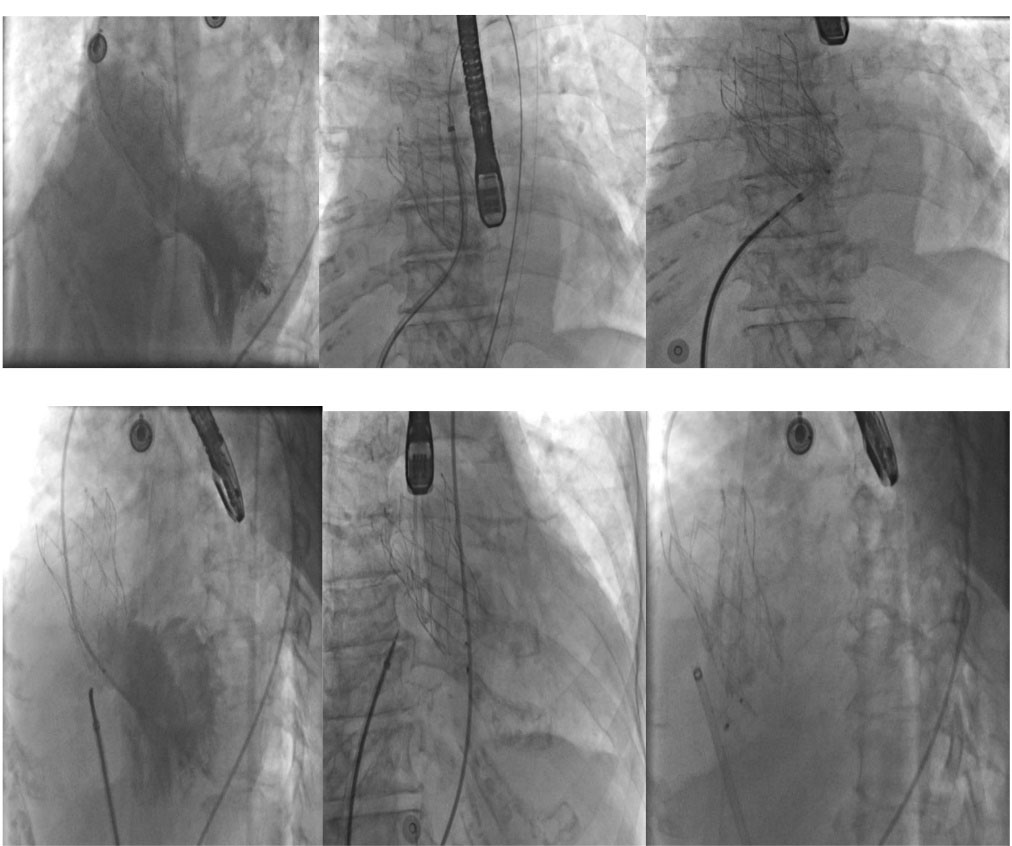

Figure 3.

Angiographic view of the percutaneous closure of the ventricular septal defect.

The patient was an active 82-year-old woman (NYHA IV) with shortness of breath at rest. Her comorbidities included hypertension and asthma history. During her examination, she was found to have normal left ventricular (LV) systolic function (ejection fraction; 60%) and severe calcific aortic valve stenosis (aortic valve area: 0.7 cm2; peak / mean gradient: 85/55 mm Hg) on transthoracic echocardiography (TTE). Coronary angiography was found to have normal coronary vessels. The patient with 5.1% STS score was decided to undergo TAVI by our Heart Team. On multi-slice cardiac computed tomography (CT), severe calcification from the aortic valve level and calcified nodule towards the LVOT were noted. Calcific nodule extending to LVOT shown in . The procedure was briefly performed as follows: A 6-F sheath was placed in the right common femoral artery and vein then proglide was inserted. A stiff wire was then inserted through a pig tail catheter. 19 F delivery catheter has been advanced from descending aorta. By performing fast pacing, a nucleus 20×40 mm balloon was predilated and a self-expandable 29 mm Portico prosthesis was implanted. At this stage, there was second grade aortic ınsufficiency (AR) and the prosthesis was postdilated with nucleus 25×40 mm balloon. After the procedure, a very good result was obtained with only minimal insufficiency and elimination of the aortic gradient. No problem developed during the follow-up during hospitalization and no obvious pathology was detected in the post-procedure follow-up echocardiography. However, a pansystolic murmur was detected in the physical examination of the patient with dyspnea at the follow-up 1 month later, and aortic Portico prosthesis (maximum gradient:11 mm Hg, minimal insufficiency) was detected on TTE. However, the right chambers were dilated with significant tricuspid regurgitation and an increased systolic pulmonary artery pressure of 60 mm Hg. In addition, a perimembranous VSD 7 mm was evident beginning from the edge of the prostetic valve, resulting in a significant left-to-right shunt. Based on these findings , it was decided to perform interventional treatment of the defect using the Amplatzer muscular VSD occluder. Right femoral artery and vein canulated using 6-F sheath. A pigtail catheter was passed to the LV. A 0.035 hydrophilic wire and 5-F JR-3.5 catheter were then passed through the VSD to the RV. The wire unintentionally went into the inferior vena cava and the catheter sent over the wire to the inferior vena cava. Then the hidrofilic wire was exchanged with a 0.035 300 cm Noodle wire. The wire was snared in the inferior vena cava and externalized through the right femoral vein. From the right femoral vein a 7-f delivery sheath sent to the ascending aorta through inferior vena cava and the VSD. VSD diameter was measured 7 mm by ventriculography and 8 mm with TOE. Later, 10 mm Amplatzer muscular VSD occluder device was sent through the long sheath, and the first disc was opened in the ascending aorta. Then the system was pulled back to the VSD and the second disc was unsheated (). On 3D-TOE the occluder device was in a correct position, and there was a minimal shunt possibly through the occluder device (). It was disconnected from the delivery cable after confirming that there was no compression or problem with the aortic valve. Two days after the procedure, the device was in a good position, there was mild tricuspid regurgitation and systolic pulmonary artery pressure was 40 mmHg (). After one week of follow-up, the patient was discharged home. It continues to be active with significant improvement in shortness of breath (NYHA I-II) twelve months after the procedure.